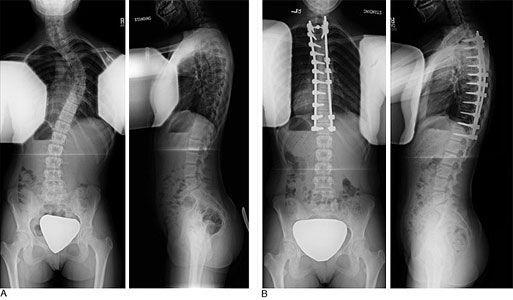

側弯手術はインプラントを用いて、カーブした脊柱を真っ直ぐに近づけるものです。

手術でどの程度真っ直ぐになるかはそれぞれということを踏まえつつ、平均的な矯正率がどのくらいなのかをみておきましょう。

結論から言うと、手術のカーブ矯正率はおおよそ【65〜75%程度】と考えられています。

これは、特発性側弯症に対する後方脊椎固定術という方法での結果です。

例として、コブ角が60°の方が手術を受けた場合、術後のコブ角は平均18°くらいになるということです。